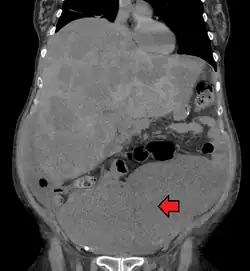

| Location and appearance of two example colorectal tumors | |

A colorectal cancer is sometimes initially discovered on CT scan.[95]

The presence of metastases is determined by a CT scan of the chest, abdomen, and pelvis.[20] Other potential imaging tests such as PET and MRI may be used in certain cases.[20] MRI is particularly useful to determine the local stage of the tumor and to plan the optimal surgical approach.[95]